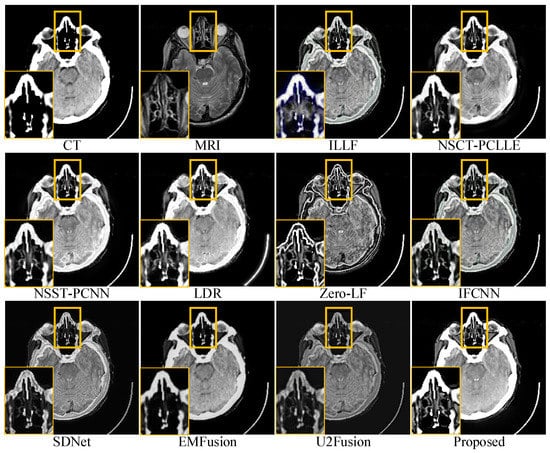

4.3. Subjective Quality Assessment

| Objective evaluation of different fused images in Figure 5 | ILLF | 0.5554 | 0.8054 | 0.1583 | 0.2049 | 5.7517 | 0.1330 |

| NSST-PCNN | 0.6502 | 0.8050 | 0.6791 | 0.3444(3) | 4.7473 | 0.2048 | |

| NSCT-PCLLE | 0.6232 | 0.8047 | 0.6962(3) | 0.2792 | 4.6168 | 0.2194(3) | |

| LRD | 0.7302 | 0.8056(3) | 0.2218 | 0.3292 | 4.5160 | 0.1702 | |

| Zero-LF | 0.7918(3) | 0.8056 | 1.5481 | 0.1172 | 4.0112 | 0.0874 | |

| IFCNN | 0.6690 | 0.8047 | 0.1469 | 0.2907 | 4.2017 | 0.1669 | |

| SDNet | 0.6513 | 0.8051 | 0.1084 | 0.2840 | 4.8154(2) | 0.1712 | |

| EMFusion | 0.8345(2) | 0.8063(2) | 0.1309 | 0.5829 | 4.2328 | 0.3247 | |

| U2Fusion | 0.6059 | 0.8045 | 0.0849 | 0.2925 | 4.4836 | 0.1862 | |

| Proposed | 0.8443 | 0.8070 | 1.1038(2) | 0.4424(2) | 4.7689(3) | 0.2293(2) | |